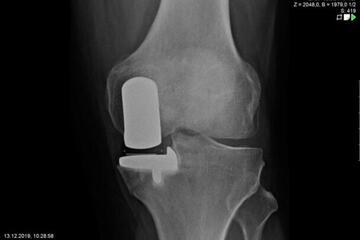

Endoprosthetics of the knee joint is an effective procedure for the treatment of symptomatic advanced wear and tear of the knee joint (gonarthrosis). If the X-ray shows a complete loss of joint space width under load, the complaints persist for more than 6 months, and the conservative therapy options have been exhausted, there is probably an indication for treatment with an artificial joint replacement (endoprosthesis). It must then be clarified which type of prosthesis is required, because today we have a large number of implants available. We distinguish between partial joints and full prostheses, and in the case of full prostheses we again distinguish between the degree of coupling of the prosthesis. If only parts of the joint are affected, only these have to be replaced and partial joints can be used. The so-called sled prostheses on the inner and outer side of the knee joint, as well as the sliding bearing replacement for problems on the kneecap, have both proven themselves effective. With full prostheses, we again differentiate between the degree of coupling of the prosthesis. Anterior and posterior cruciate ligament-supporting prostheses (surface replacement) partially coupled implants that support the inner and outer ligaments and coupled implants for complete loss of knee ligament and capsular function are used. Partially and fully coupled prostheses usually have to be inserted with stem components.

The knee prostheses are usually cemented in place, but cement-free implants are also available, which can be used, for example, in cases of cement allergies or very young patients.